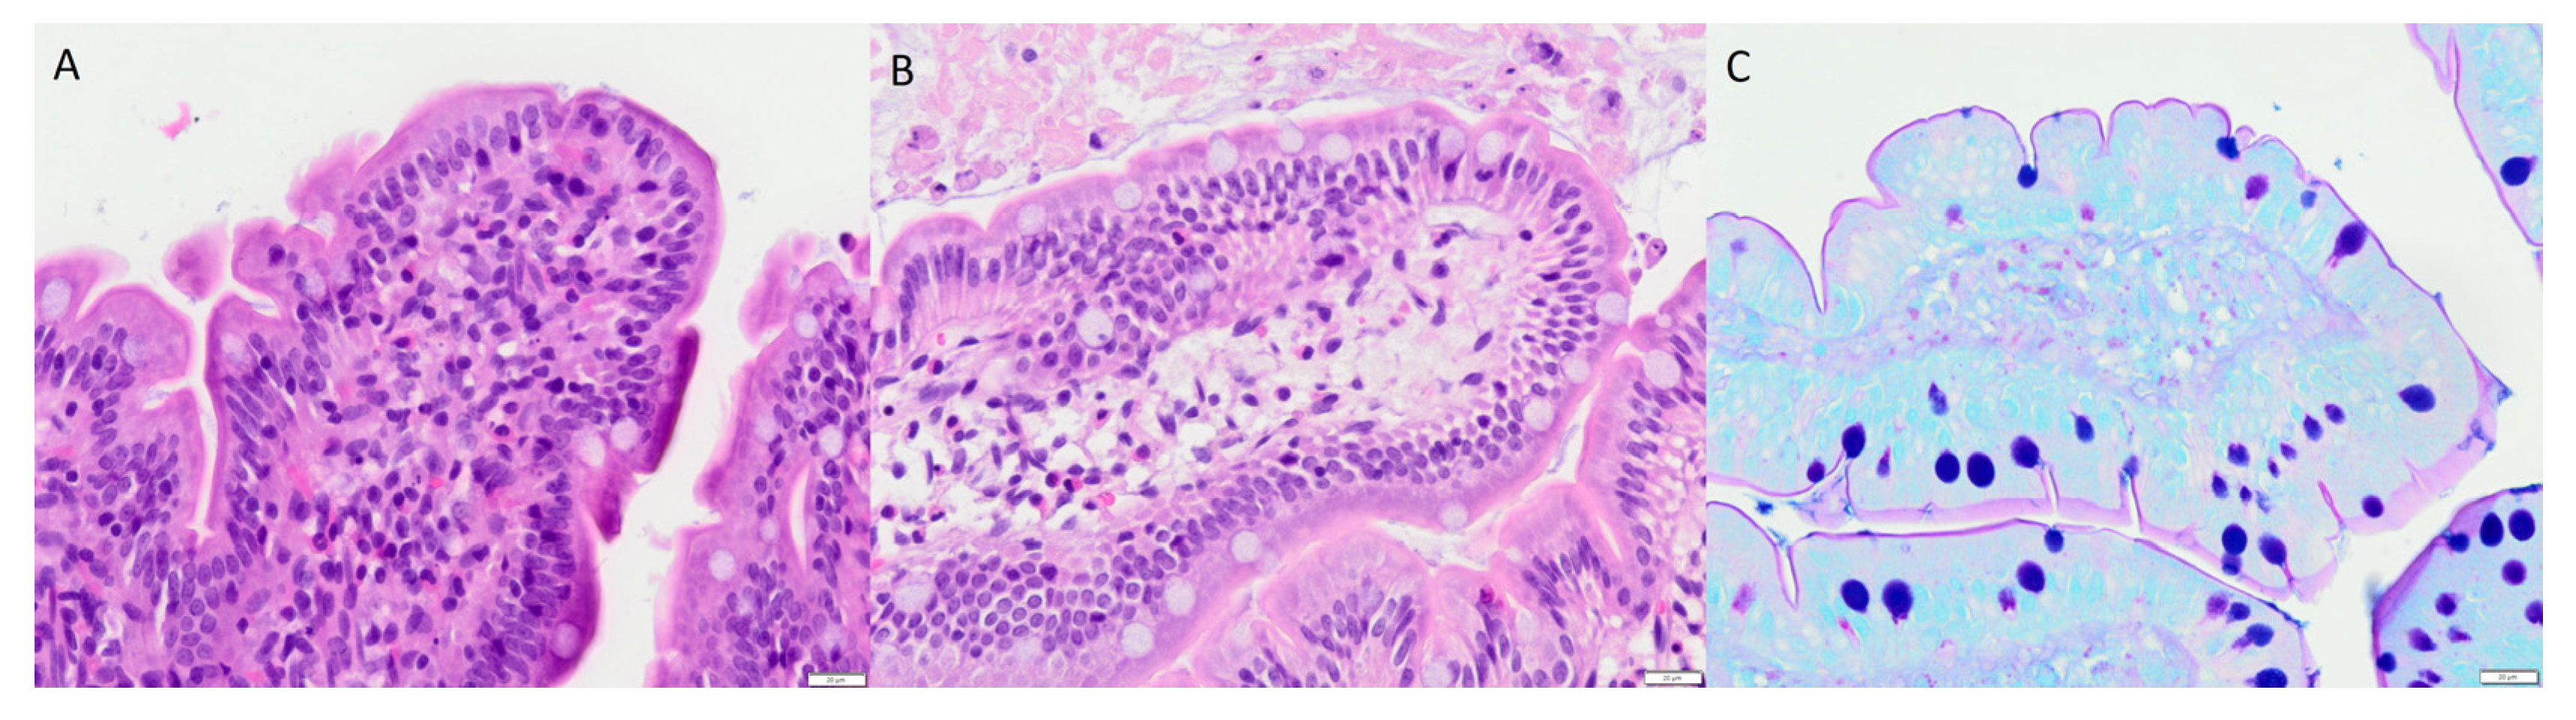

2.6. Histology

4.6. Histology